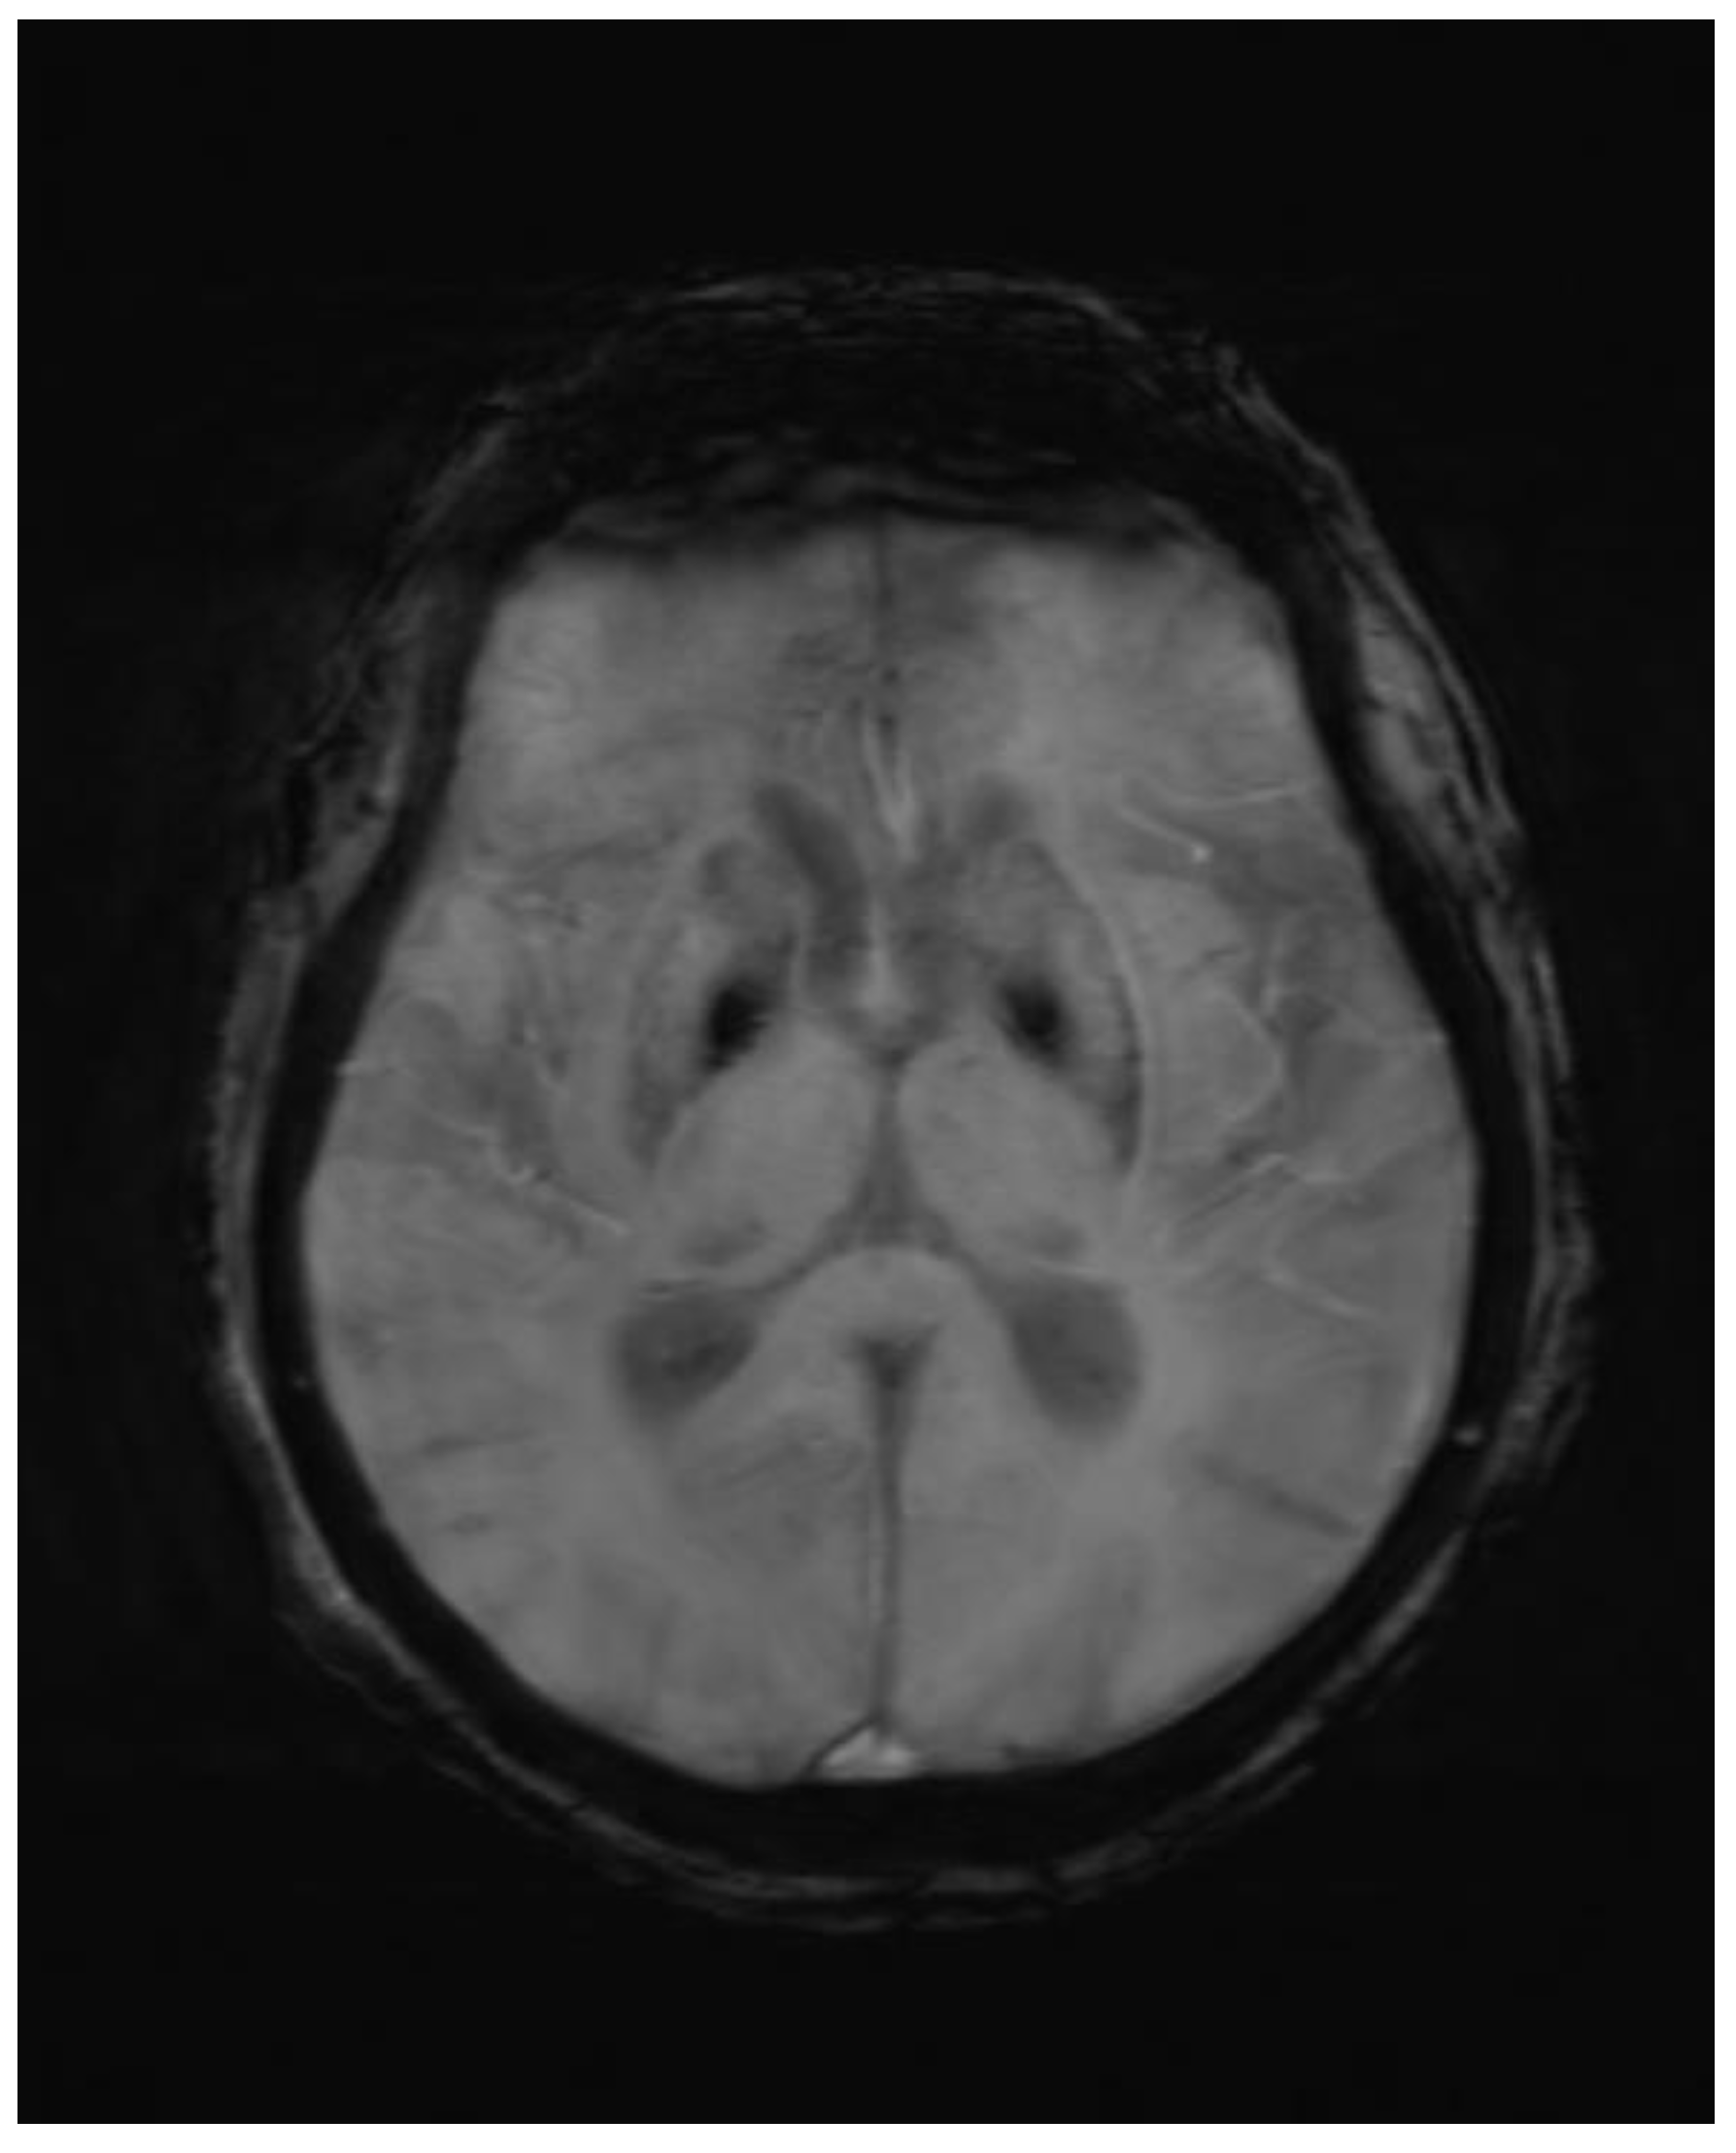

Abnormal symmetrical T1WI hyperintensity was noted in bilateral putamen. Subtle areas of GRE blooming were visible. Dilatation of ventricular system, cerebral sulci, basal cisterns and cerebellar folia were visible which suggested cerebral and cerebellar atrophy. Few discrete T2WI and FLAIR hyperintensities were noted in bilateral periventricular deep white matter in fronto-parietal region, which were suggestive of chronic ischemic changes

Figure 1. Axial GRE image showing blooming in corresponding T1 hyperintense area.

Figure 2. Axial T1wi sequence showing bilateral symmetrical hyperintensity in putamen.